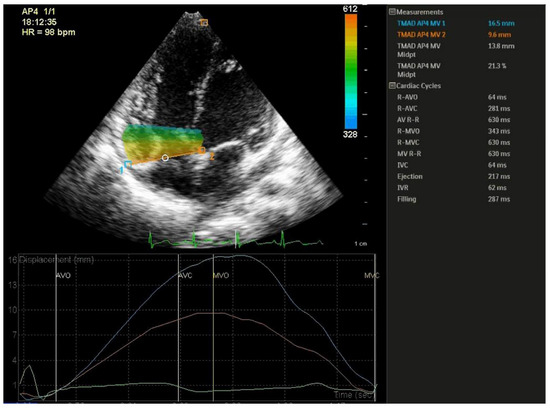

2.3. TMAD Data Acquisition and Analysis

3.3. TMAD Analysis

| TMAD lat (mm) | 19.08 ± 3.88 | 14.90 ± 2.37 | 11.64 ± 2.84 | 0.006 | 0.0001 | 0.106 |

| TMAD sept (mm) | 12.29 ± 2.25 | 8.51 ± 1.82 | 7.63 ± 2.09 | 0.0001 | 0.0001 | 1.000 |

| TMADmid (mm) | 16.38 ± 2.96 | 12.15 ± 2.13 | 10.44 ± 3.59 | 0.001 | 0.0001 | 0.603 |

| TMADm% | 23.70 ± 3.62 | 18.13 ± 2.87 | 13.51 ± 2.84 | 0.0001 | 0.0001 | 0.010 |